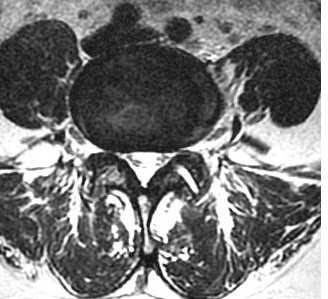

МРТ позвоночника. Аксиальная Т2-взвешенная МРТ. Нормальный срез через дугоотростчатые суставы.

После того, как появилась ясность в способе получения МРТ изображений позвоночника, надо понять какие анатомические структуры видны. Счет позвонков ведется разными способами - сверху от зубовидного отростка С2 (осевой позвонок), от бифуркации трахеи Т5 ( пятый грудной, с погрешностью на 1 позвонок) или снизу от L5 (последний поясничный), также не исключена погрешность на 1 позвонок в связи люмбализацией или сакрализацией. Анатомия позвоночника в МРТ изображении представлена в нашей другой статье. На серии сагиттальных Т2-взвешенных МРТ позвоночника видны асе основные структуры, причем удается проследить ход корешков конского хвоста. В поясничном отделе он идет под углом вниз и выходит через межпозвоночное отверстие нижележащего позвонка. Аксиальные (поперечные) МРТ срезы всегда делаются вдоль межпозвоночного диска, то есть с учетом нормальных или патологических изгибов позвоночника. Они наиболее удобны для оценки состояния дугоотростчатых суставов. При МРТ позвоночника в поперечной плоскости МРТ срезы часто делают на разных уровнях для лучшей визуализации состояния корешков по их ходу - в дуральном мешке, затем боковом кармане дурального мешка, далее в межпозвоночном отверстии и, наконец, после выхода из него. Таким образом, в поперечном МРТ срезе позвоночника через межпозвоночное отверстие на поясничном уровне можно видеть отрезки сразу двух корешков - вышележащего на выходе из отверстия, и нижележащего в боковом кармане.

МРТ поясничного отдела позвоночника. Остеоартрит и остеоартроз дугоотростчатых суставов. Аксиальная Т2-взвешенная МРТ.

МРТ поясничного отдела позвоночника. Синовиальная киста справа. Аксиальная Т2-взвешенная МРТ.